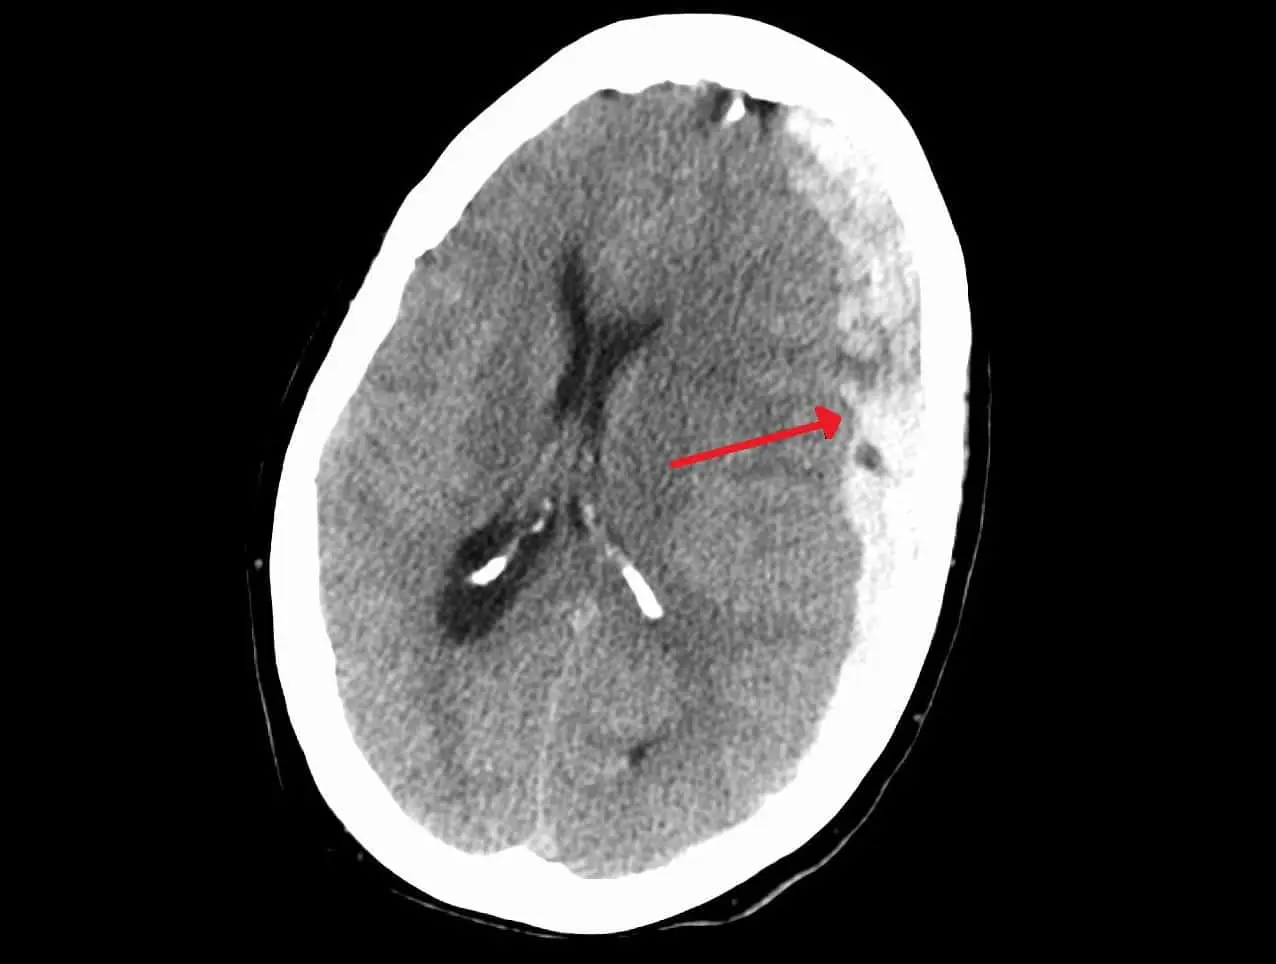

Травматическая субдуральная гематома — одно из наиболее серьезных и частых осложнений черепно-мозговых травм, особенно среди пожилых пациентов. При этом патологическом процессе кровь, просачиваясь из поврежденных сосудов, начинает скапливаться между мозгом и внутренней поверхностью черепа. Такое давление может вызвать тяжелые неврологические нарушения, а в ряде случаев и угрозу жизни. С годами риск подобных осложнений возрастает, поскольку мозг становится более подверженным травмам, а распространенное использование антикоагулянтов — препаратов, предотвращающих образование тромбов — увеличивает вероятность геморрагических осложнений даже после незначительной травмы.

Исследование охватило пациентов, поступивших с диагностированной субдуральной гематомой в течение первых шести часов после происшествия. Используя современные методы лучевой диагностики, ученые распределили всех пострадавших на три группы в зависимости от расположения гематомы: лобно-височная, теменно-височная и лобно-теменно-затылочная области. Такой классификации удалось достичь благодаря оперативной диагностике и полной картине травмы.

Результаты оказались красноречивыми: наиболее благоприятные прогнозы были у пациентов с лобно-височными кровоизлияниями — именно эта локализация обеспечила 35% всех успешных исходов. В то же время при гематоме, расположенной в лобно-теменно-затылочной области, часто наблюдались более тяжелые формы повреждений, больший объем гематомы и выраженная неврологическая симптоматика, что усложняло лечение и увеличивало риски.